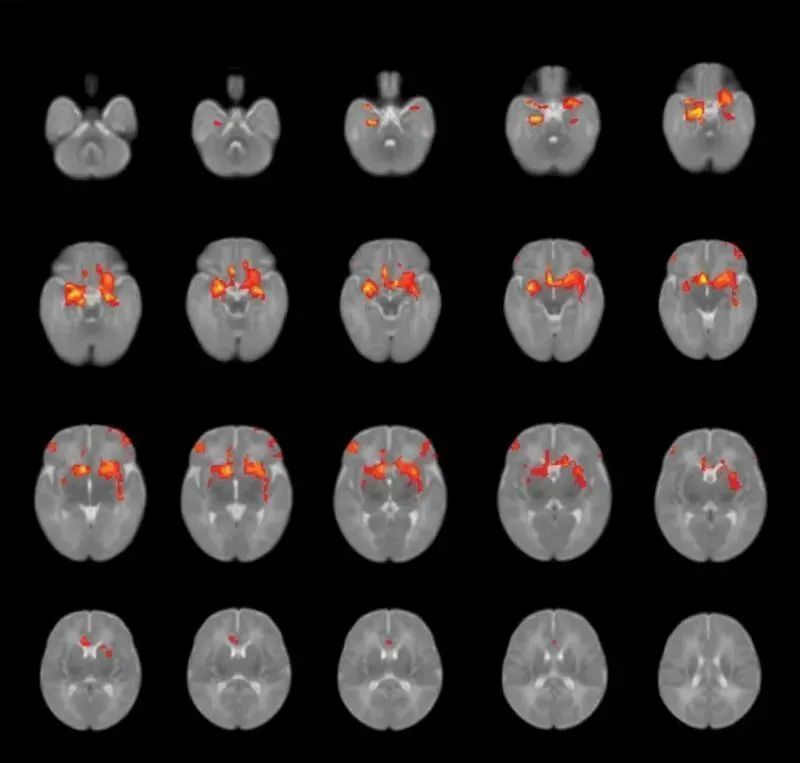

他们在对出生后3个月的婴儿大脑进行磁共振成像扫描后发现,孕期焦虑或抑郁较严重的妈妈似乎会影响胎儿大脑的神经连接。

▲研究人员查看了婴儿大脑中杏仁核(参与情绪处理的脑区)与其他脑区的连接